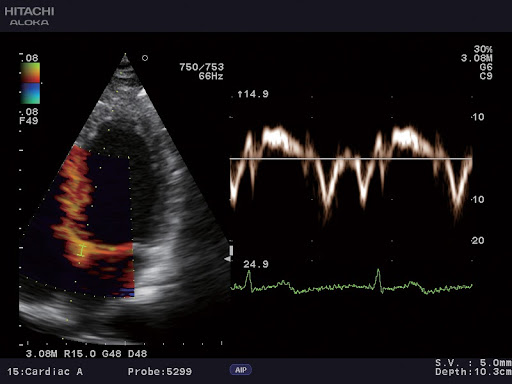

- Блок ЭКГ

- Постоянно-волновой допплер

Тканевый допплер

EUP-S50A – Датчик для проведения эхокардиографических исследований взрослых. Также подходит для транскраниальной допплерографии.